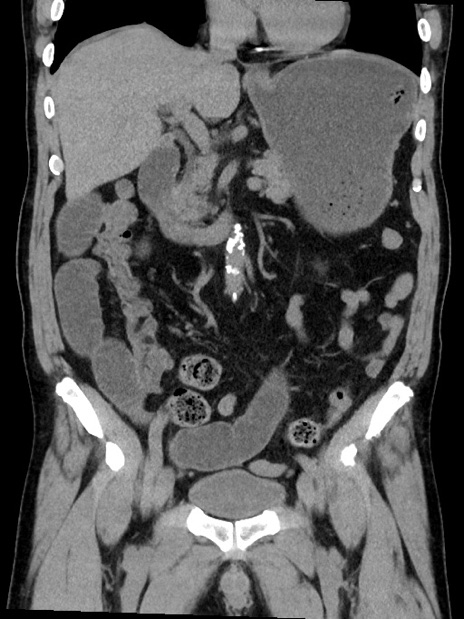

症例35(冠状断像)

【症例】70歳代 男性

【主訴】腹部膨満、嘔吐

【現病歴】昨日より腹部膨満感出現。本日増悪し、仙痛出現。嘔吐あり、受診。

【既往歴】糖尿病、胆摘後

【身体所見】BP 149/80mmHg、HR 74/min、BT 35.9℃、腹部:膨満、軟、圧痛なし。腸雑音減弱あり。上腹部正中切開瘢痕あり。

【データ】WBC 13500、CRP 1.72